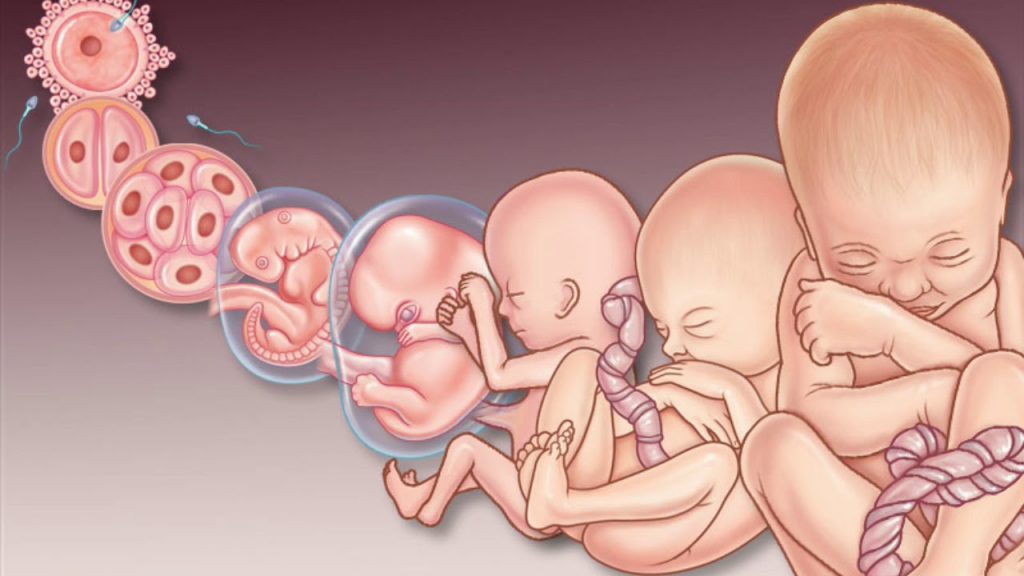

Загадочные образы животных в утробе матери

Раздел: Другие животные